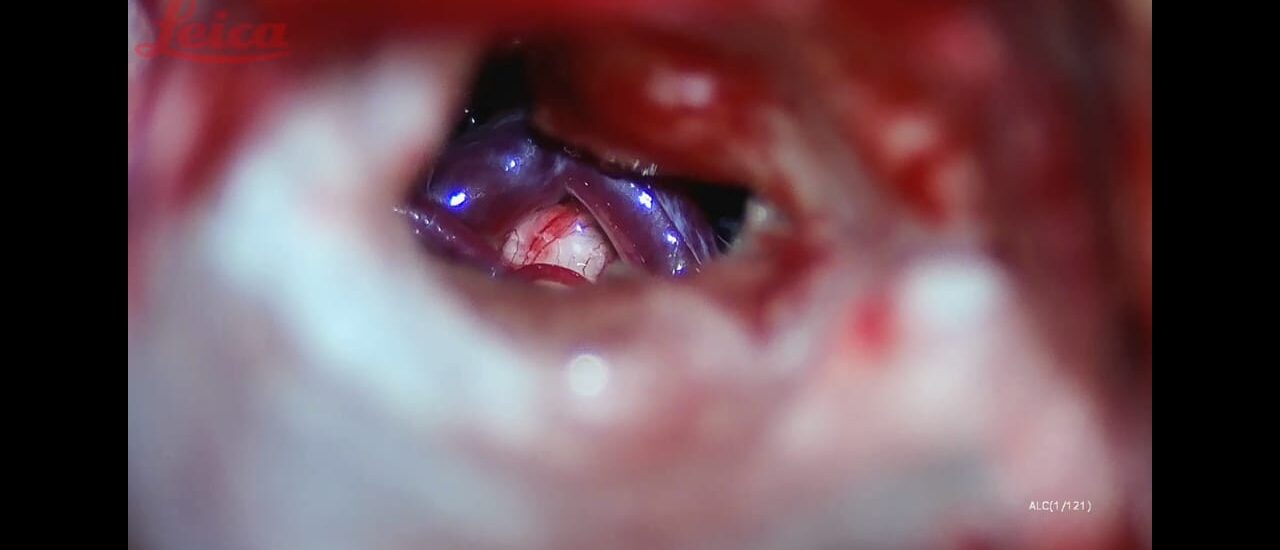

Lminectomy C3 down to C6 augmented by lateral mass fixation

Male 55 year daibetc known CSM operated 5 years by C5 C4 lamenectomy Pre operative Presented by progressive mylopathy VAS neck pain 8JOA score 9Preoperative radiologyCanal stenosis adjacent segment disease reversed cervical kyphosis. Global sagittally imbalanceOperated by extended laminectomy C3 down to C6 augmented by…